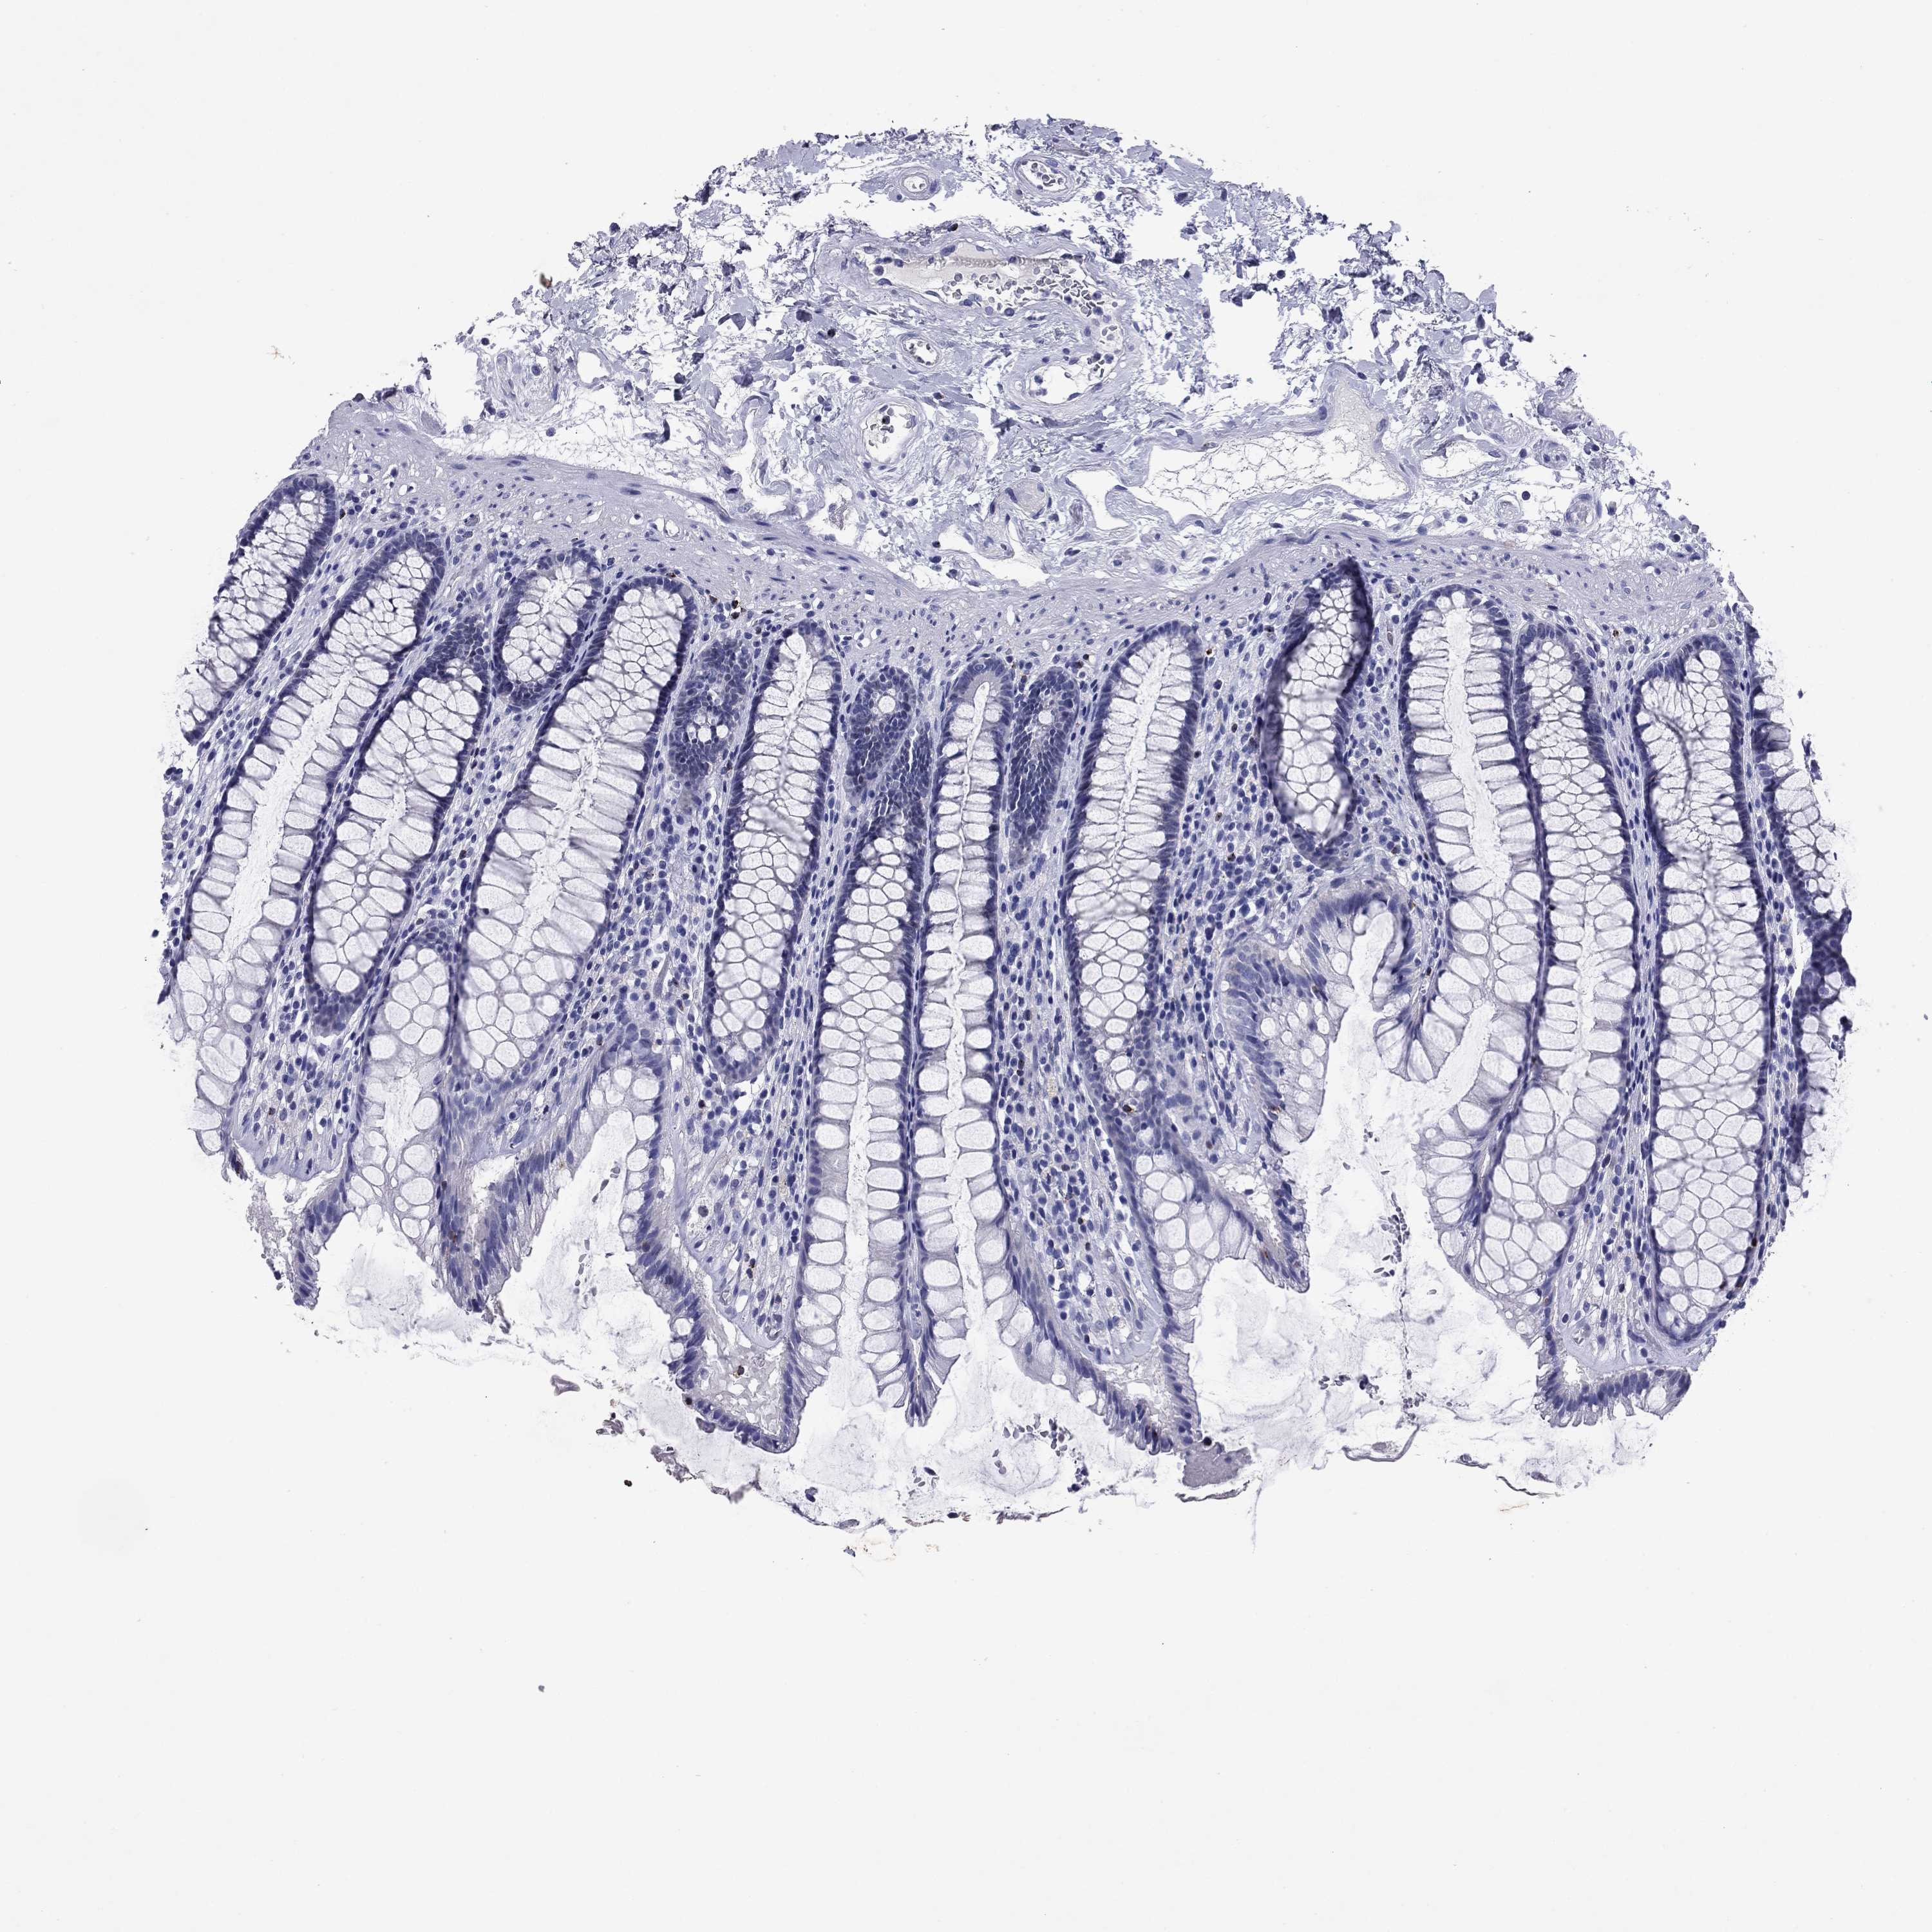

TISSUE PRIMARY DATA RECTUM Show tissue menu

RECTUM - Antibody stainingi

Antibody staining in the annotated cell types in the current human tissue is reported as not detected, low, medium, or high, based on conventional immunohistochemistry profiling in selected tissues. This score is based on the combination of the staining intensity and fraction of stained cells.

Each image is clickable and will lead to virtual microscopy that enables deeper exploration of all samples and also displays staining intensity scores, fraction scores and subcellular localization as well as patient and tissue information for each sample.

Antibody HPA063181Antibody HPA065895

Glandular cells Not detectedNot detected